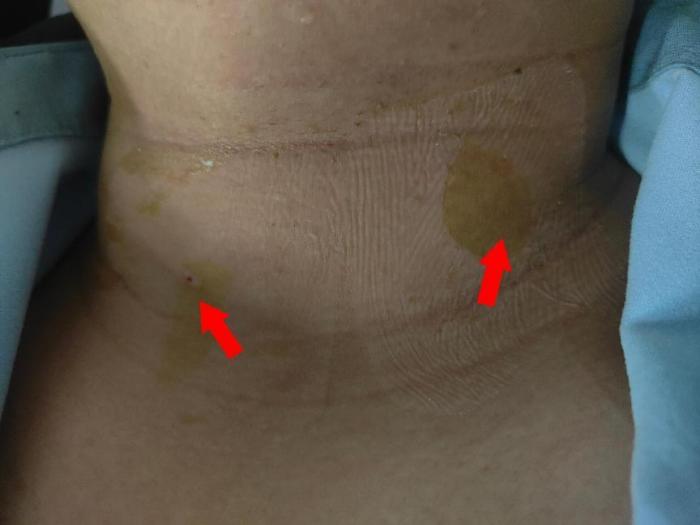

甲状腺微波消融术后皮肤仅见针孔大小伤口且无明显出血